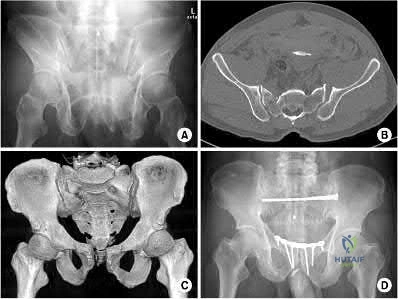

A 29-year-old obese patient is transferred from an outside facility for the management of a closed-head injury and the fracture shown in Figure A. He presents to the trauma bay as a transient responder to blood products, and undergoes urgent pre-surgical angiography embolization. Surgery is performed within 8 hours from the time of injury. The patient develops a deep wound infection 1 week post-operatively. Which of the following factors would be considered the MOST statistically significant predictor for post-operative infection in this patient.

Figure A shows an AP radiograph and 3D CT reconstruction of a APC3 pelvic ring fracture.

Based on the Young and Burgess classification of pelvic ring injuries, an anterior-posterior compression type II injury does not result in disruption of which of the following?

Young and Burgess classification of pelvic ring injuries is largely based on the mechanism and energy of injury. An APC type I involves slight widening of

pubic symphysis and/or anterior sacroiliac (SI) joint. An APC II is a continuation of this force, and additionally involves a disrupted anterior SI joint, as well as sacrotuberous and sacrospinous ligaments. An APC III also involves disrupted posterior SI ligaments, causing complete SI joint disruption with potential translational and rotational displacement.

The reference by Young et al is a classic article that describes the Young and Burgess classification of pelvic ring injuries. They retrospectively analyzed pelvic ring radiographs and discussed four patterns of injury: anteroposterior compression, lateral compression, vertical shear, and a complex/combined pattern.

The reference by Burgess et al is a validation of the aforementioned classification and study, as they reviewed 210 consecutive patients who sustained a pelvic ring injury. They validated the classification scheme and found that overall blood replacement averaged: lateral compression, 3.6 units; anteroposterior compression, 14.8 units; vertical shear, 9.2 units; combined mechanical, 8.5 units. Overall mortality was: lateral compression, 7.0%; anteroposterior, 20.0%, vertical shear, 0%; combined mechanical, 18.0%.

Illustration A shows an APC-II injury pattern - (a) is an outlet radiograph, (b) is an axial CT cut, (c) is a 3-D CT cut, and (d) is a representative fixation construct.